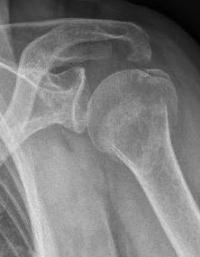

Proximal Humeral Fracture

The proximal or shoulder-joint humeral fracture accounts for 5% of all fractures and is a typical fracture of the elderly. Often it is associated with osteoporotic bone changes, so that even a small trauma leads to breakage. It occurs in younger patients, usually as a result of a high speed impact injuires.

The most common form is the subcapital humeral fracture just below the humeral head, but also the humeral head can be directly affected.

The first indication of a proximal humeral fracture is provided by the accident. Typical is a fall on the shoulder or the arm, also as indirect trauma with fall on the outstretched hand or the elbow. Furthermore, a physical examination is indispensable for the diagnosis of the above symptoms. The shoulder should be x-rayed in 3 planes. Sometimes, a supplementary computer tomography is necessary for further diagnosis and exact determination of the course of the fracture. Magnetic resonance imaging is only performed if there is a suspicion of a dislocation of the shoulder joint or a malignant underlying disease as the cause of the fracture.

There are many different classifications for the codification of proximal humeral fractures. A frequently used classification is NEER. Depending on the displacement, tilting and exact localization of the fracture clefts, the classification is divided into a total of 6 classes (NEER I - VI).

Proximaler Oberarmbruch5Proximaler Oberarmbruch6

Picture: Here is a subcapital upper arm break in a young woman. An angle stable plate osteosynthesis was performed to stabilize the head in correct position to the humeral shaft and shoulder joint. Especially in young patients, We strive to treat non-invasively and as gently as possible. This possibility is often due to the bone quality in young as opposed to older people.